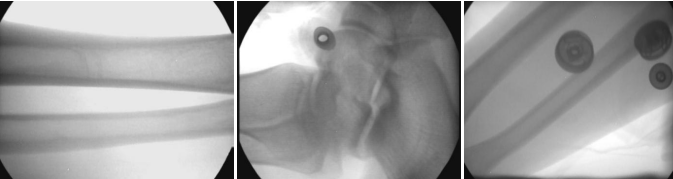

7:拍攝效果圖